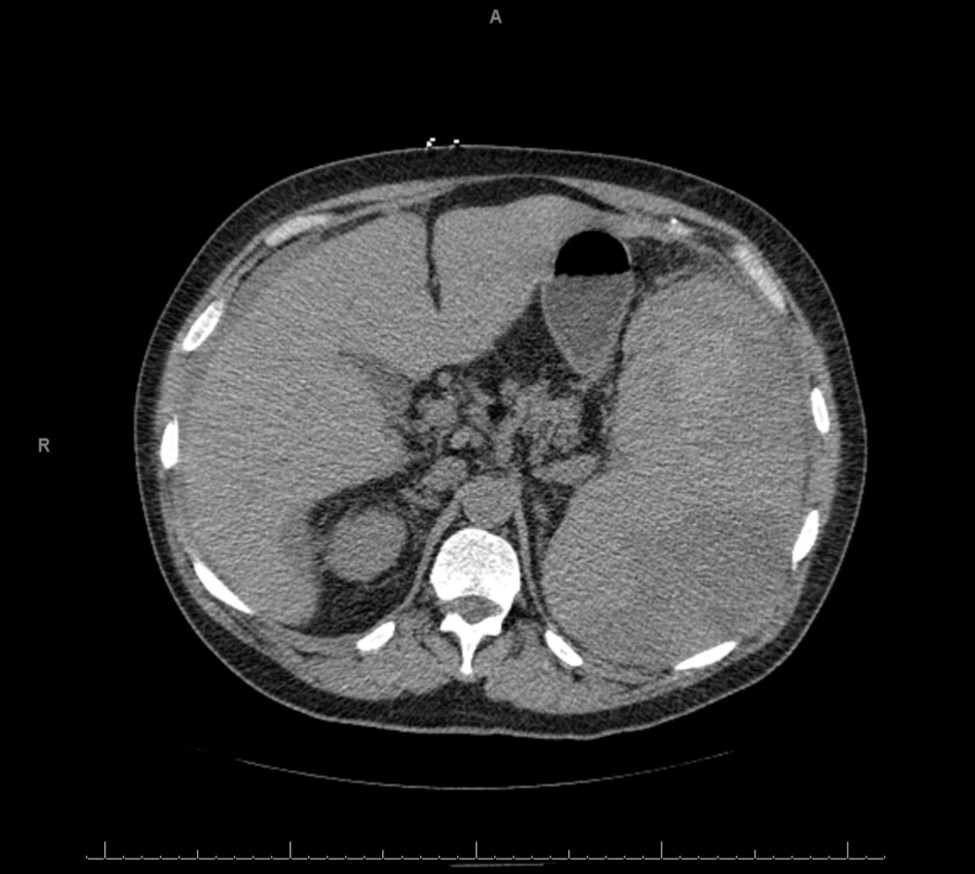

A plain abdominopelvic CT showed massive splenomegaly with high attenuation areas suspicious for hematoma, as well as free fluid in the abdomen (Figure 1). The patient was immediately started on a transfusion of packed red blood cells and taken emergently to the operating room. A laparotomy was performed and the patient was found to have a massive, ruptured spleen with 1500 mls of frank blood in the peritoneal cavity. Splenectomy and abdominal washout were done. The spleen measured 21 x 19 x 10 cm and weighed 2870 grams. It is shown below (Figure 2).

Figure 1.CT image of the abdomen showing the enlarged spleen. The arrows point to areas of higher attenuation suspicious for hematoma